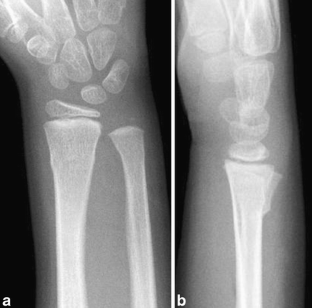

Fig. 1